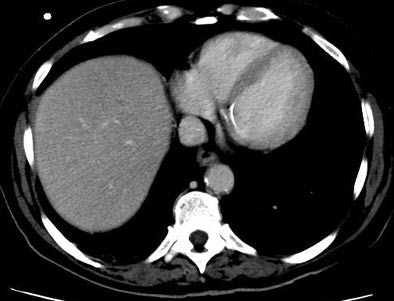

| Patient with fever after prolonged neutropenia. Above, arterial-phase CT of liver shows a type 2b lesion (arrow). Unenhanced CT (below) shows a corresponding hypoattenuating lesion, while portal-venous-phase CT (bottom) shows a tiny nonspecific hypodensity (type 1 lesion). This case demonstrates how arterial-phase CT adds specificity. Although portal-venous phase depicted the lesion, it would be extremely difficult to "call" it an abscess. The enhancement pattern on arterial phase CT makes for a more confident diagnosis. All images courtesy of Dr. Ur Metser. |

Metser and colleagues retrospectively examined 60 bi- or triphasic CT exams in the 39 immunocompromised patients with suspected fungal hepatic infections. CT images of the liver were acquired at 120 kVp, 230-330 mAs, table speed of 0.5 mm per rotation, high-quality mode, and pitch of 3:1. CT data were reconstructed using 5-mm-thick slices with 50% overlap. Nonionic intravenous contrast material was administered with the use of a power injector at a dose of 2 mL/kg up to a maximum of 200 mL, at a rate of 3 mL/sec with a 25-second delay for arterial phase, and 60-second delay for portal venous phase.

A phase was considered positive if at least three type 1 lesions, and one type 2 to 4 lesions, were identified. A study was considered positive if at least one of its phases was positive. And based on the available literature on fungal infections of the liver, type 2 and 4 lesions were classified as "lesions suggestive of infection," Metser said.

- Type I: hypoatteunating (Ia= sub-centimeter in diameter; Ib= at least 1 cm in diameter);

- Type II: hypoatteunating center with a hyperatteunating rim (IIa= thickness of hyperatteunating rim equal to or less than the radius of hypoatteunating center; IIb = thickness of hyperatteunating rim is greater than radius of hypoatteunating center);